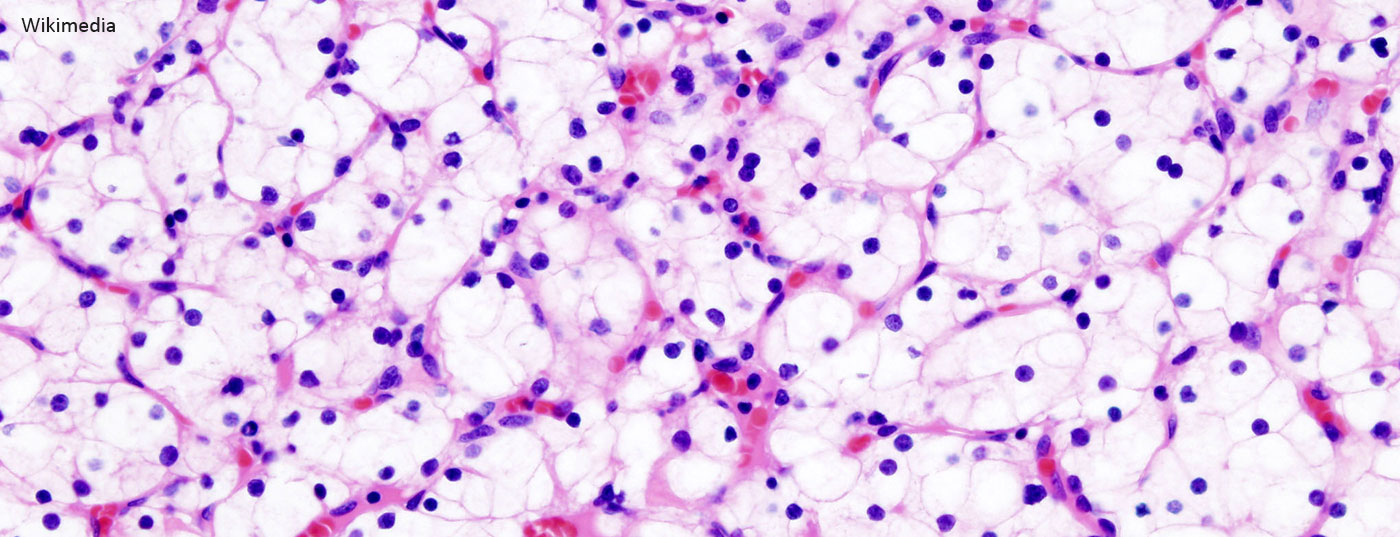

nierenkrebs_nierenkarzinom_wikimedia-free

Patienten mit operablem Nierenzellkarzinom müssen auch nach der ­Nephrektomie weiter beobachtet werden. Gemäss einer Studie aus dem Umfeld der renommierten Mayo-Klinik in Rochester lässt sich die notwendige Dauer der Nachsorge nach Nephrektomie mithilfe eines Risikomodells adäquat und individuell bestimmen [1]. Die Frage lautet: Ab wann übersteigt das Risiko eines anderweitigen Todes (der nicht mit dem Nierenzellkarzinom in Verbindung steht) das Risiko für ein ­Rezidiv? Dies untersuchten die Forscher anhand der Parameter Alter, Tumorstadium, Rezidivort und Komorbidität. Es zeigten sich erstaunliche Unterschiede innerhalb der Patientengruppen. Eine andere ­Studie, die am 67. Kongress der DGU vorgestellt wurde, widmete sich der prognostischen Unterscheidung von Patienten mit einem Nierenzellkarzinom im Stadium pT3 [2].